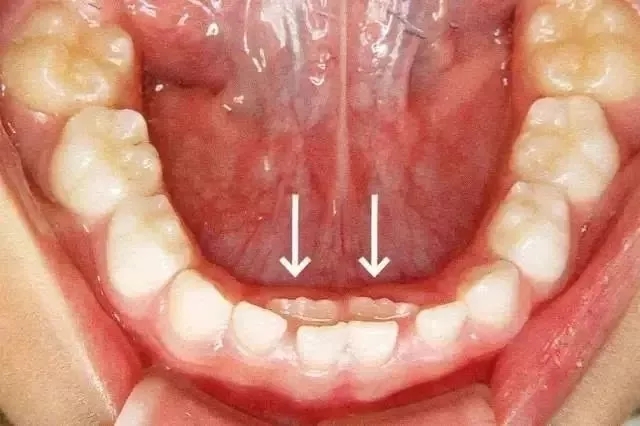

這種孩子乳牙還沒脫落,新牙就長出來的現(xiàn)象,就是所謂的“雙排牙”現(xiàn)象。也就是醫(yī)生常說的“乳牙滯留”。

箭頭所指為恒牙